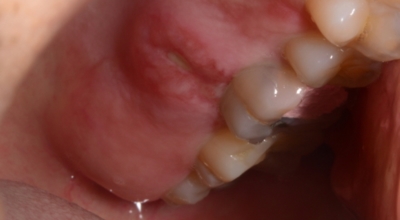

7. 구내염 원인 - 편평태선 구내염

피부에 발생되는 편평 태선등의 것으로 자가면역질환의 한 가지로 알려져 있답니다. 주로 유전적인 원인 및 면역 반응의 이상으로 나타나는 구내염으로 거미줄처럼 실선이 얽기 설기는 형태로 구내염이 발생해요. 발생 원인이 명확하지 않아 치료가 어려우나 스테로이드 연고제를 통해 증상을 완화할 수 있습니다. 이런 형태의 구내염이 긴 시간 지속될 경우 구강암으로 발전할 수 있기 때문에 필수로 병원에서 진료를 받아봐야 해요.